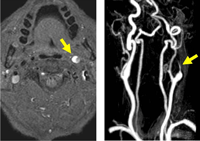

Figura 14. RM axial cervical T1 con supresión grasa (izda) que muestra disección carotídea izquierda y angioRM cervical con contraste (dcha) mostrando el característico afilamiento postbulbar de carótida interna izquierda. (flecha)